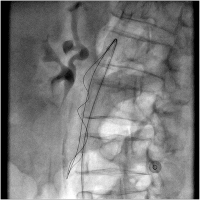

A. mesenterica superior

Abbildung 2: Retrograde Darstellung der A. mesenterica superior mit Verschluss ca 5. cm nach dem Ursprung

Keywords:

Angiologie

,

Arteria mesenterica superior

Gefäßmedizin